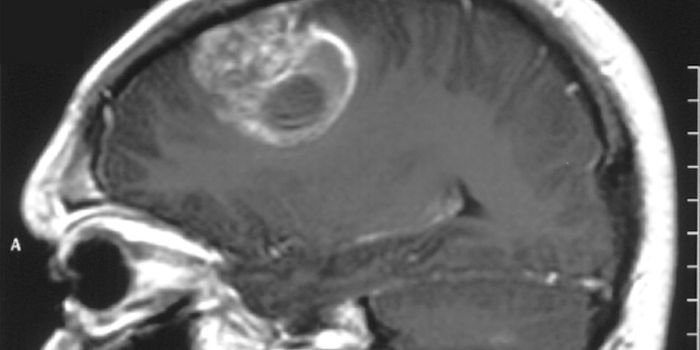

Read the latest articles about newly released neuroscience research and advances in experimental techniques. Topics include research news in neuroscience, neurology, psychology, brain science and cognitive sciences.